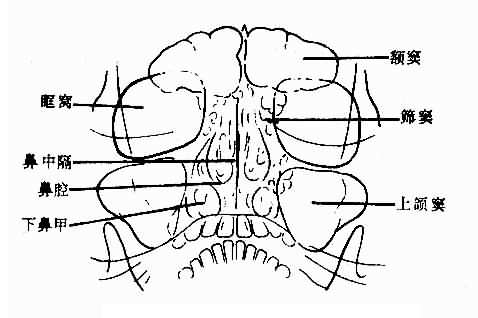

平片是检查鼻窦的基本方法。一般取坐位,鼻窦显示较好,且可查出鼻窦内积液。常用枕颏位,可显示两侧额窦筛窦上颌窦及鼻腔。正常所见,见图5-2-4。

正常鼻窦

图5-2-4 正常鼻窦(枕颏位)

额窦:多呈扇形,腔内可有骨性间隔。窦腔透明度因骨壁各部厚薄不同而不均。大小及形状个体差别较大,两侧多不对称。一侧或两侧可不发育或发育不良。

筛窦:呈蜂窝状居鼻中隔两侧和眼眶之间,其外壁为眼眶内壁。枕颏位上,蜂窝上部为前组窦,蜂窝下部为后组筛窦。蜂窝小房透明,间隔清晰、锐利,两侧多较对称。

上颌窦:居眶下方,鼻腔外侧,呈尖向下的三角形。上颌窦较透明。如嘴唇较厚,与下部重迭,可使窦腔下部密度较大,鼻翼较大,可从内壁上中部向窦腔内突入呈半圆形软组织重迭影,两侧对称,不难确认。岩骨可投影于窦腔下部,使窦腔下部密度高,不可误认为液面。两侧上颌窦的大小、形状和透明度多对称,有时一侧较小,透明度较低。

蝶窦:用颏顶位观察。呈近似椭圆形透明影,窦腔清晰、锐利。大小及外形个体差别较大,两侧可不对称。

鼻腔:鼻腔透明,鼻中隔为纵行致密带影,近于中线,多稍向一侧弯曲,上鼻甲不易显示,中鼻甲骨片垂直,下鼻甲骨片卷曲。鼻甲粘膜厚,由气体衬出。鼻甲大小个体差别较大,两侧可不对称。